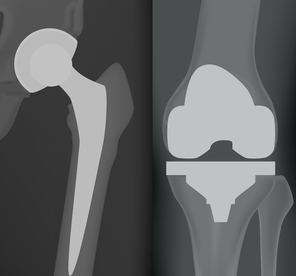

Mi Prótesis, es una aplicación especialmente dirigida a pacientes con artrosis de cadera o rodilla y a los que van a ser intervenido de una prótesis de cadera o rodilla.